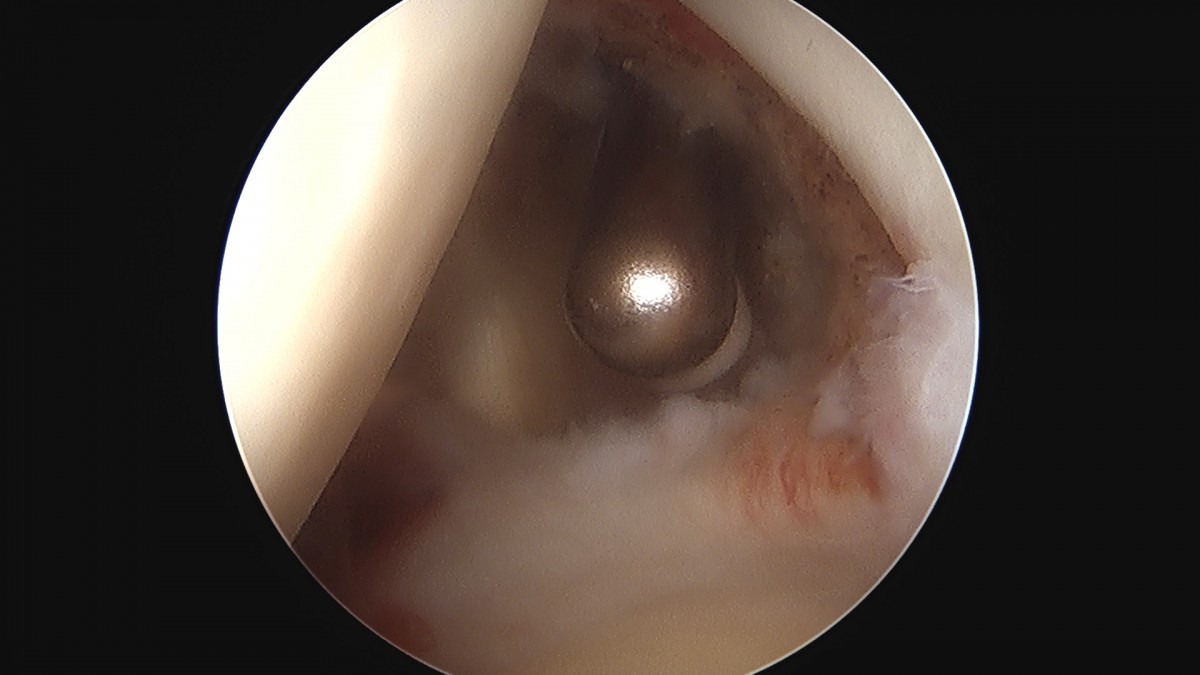

이재상원장님 어깨 견봉하 감압술 김봉O 환자

dae765e4d9ac96aee867c9d6292d8784_1758004118_8153.jpg